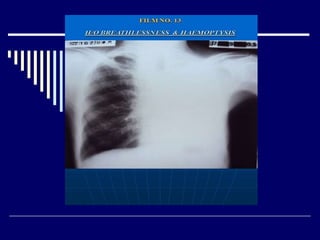

Findings

X-ray chest PA view of adult male (01)

Cystic shadows in both lower zones (02)

Dextrocardia with blurring of cardiac outline (02)

Diagnosis: - Dextrocardia with bilateral bronchiectasis (02)

(Kartagener's syndrome ) (02)

Advised: -X-ray PNS (01)

Findings X-ray chest PAview of adult male (01) Cystic shadows in both lower zones (02) Dextrocardia with blurring of cardiac outline (02) Diagnosis: - Dextrocardia with bilateral bronchiectasis (02) (Kartagener's syndrome ) (02) Advised: -X-ray PNS (01)